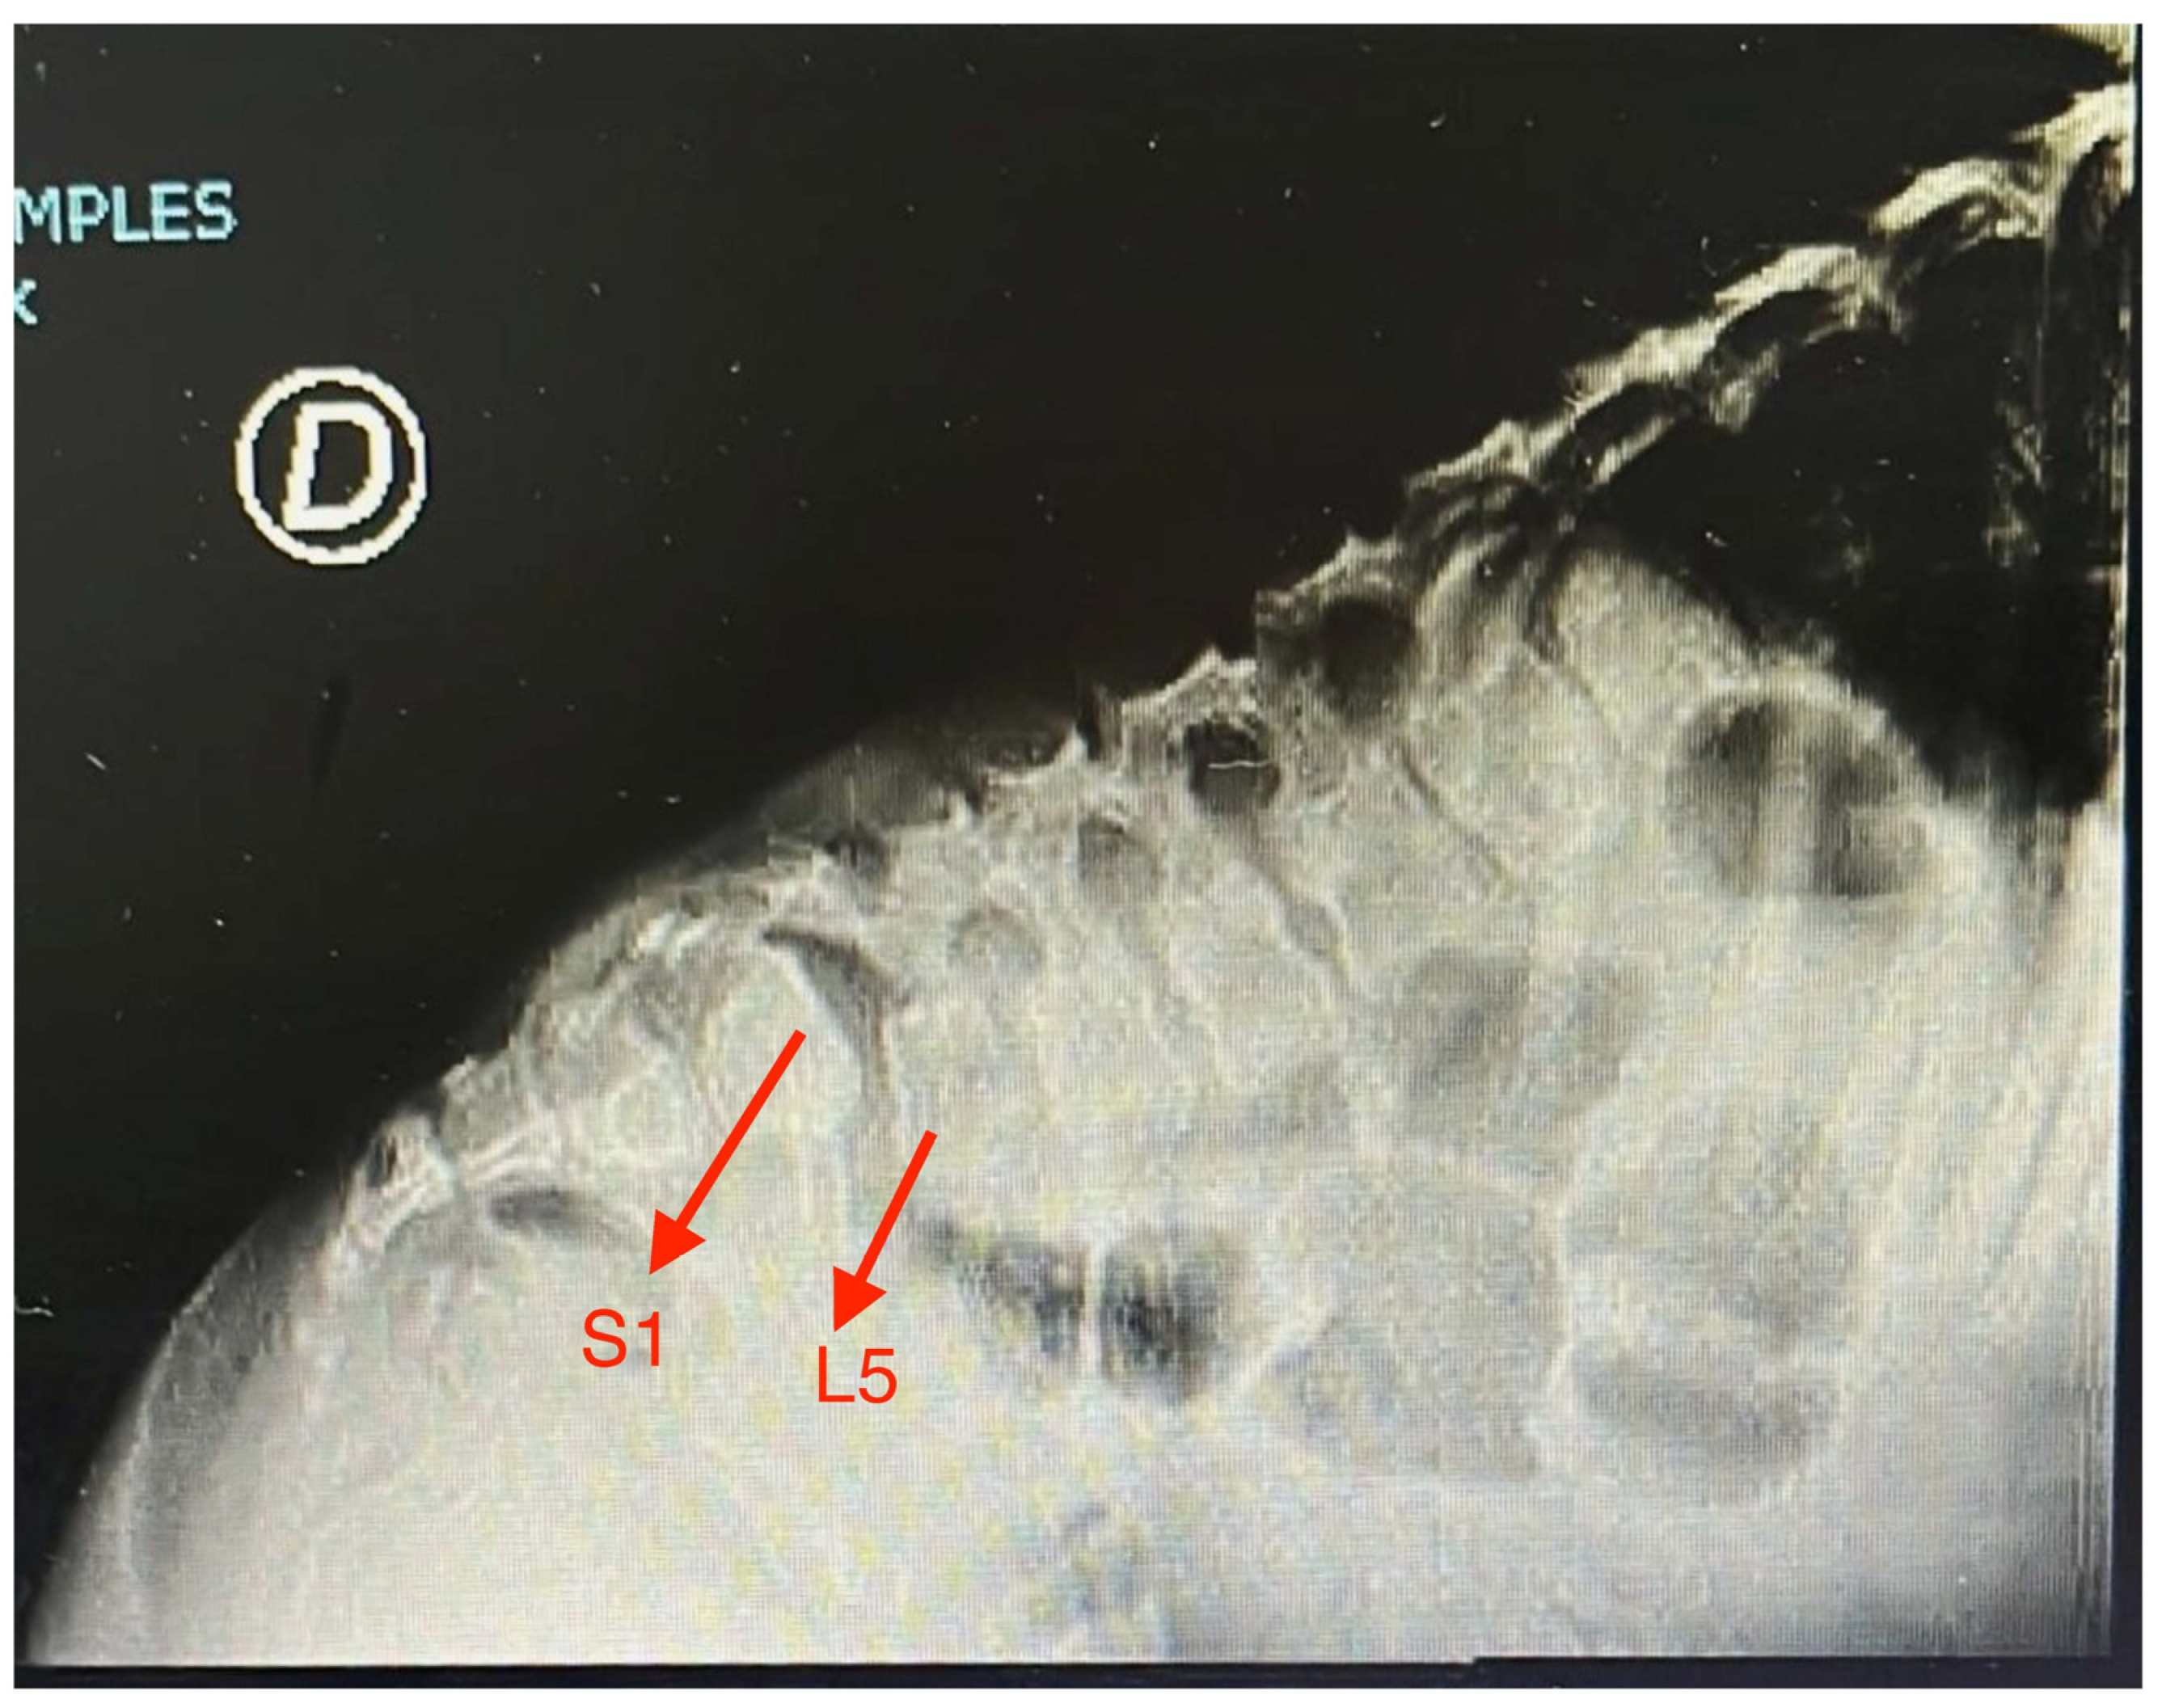

| Anterolisthesis of L5 on S1 | Yes | No | No | No | No | No | No | No | No | Yes | 20 |